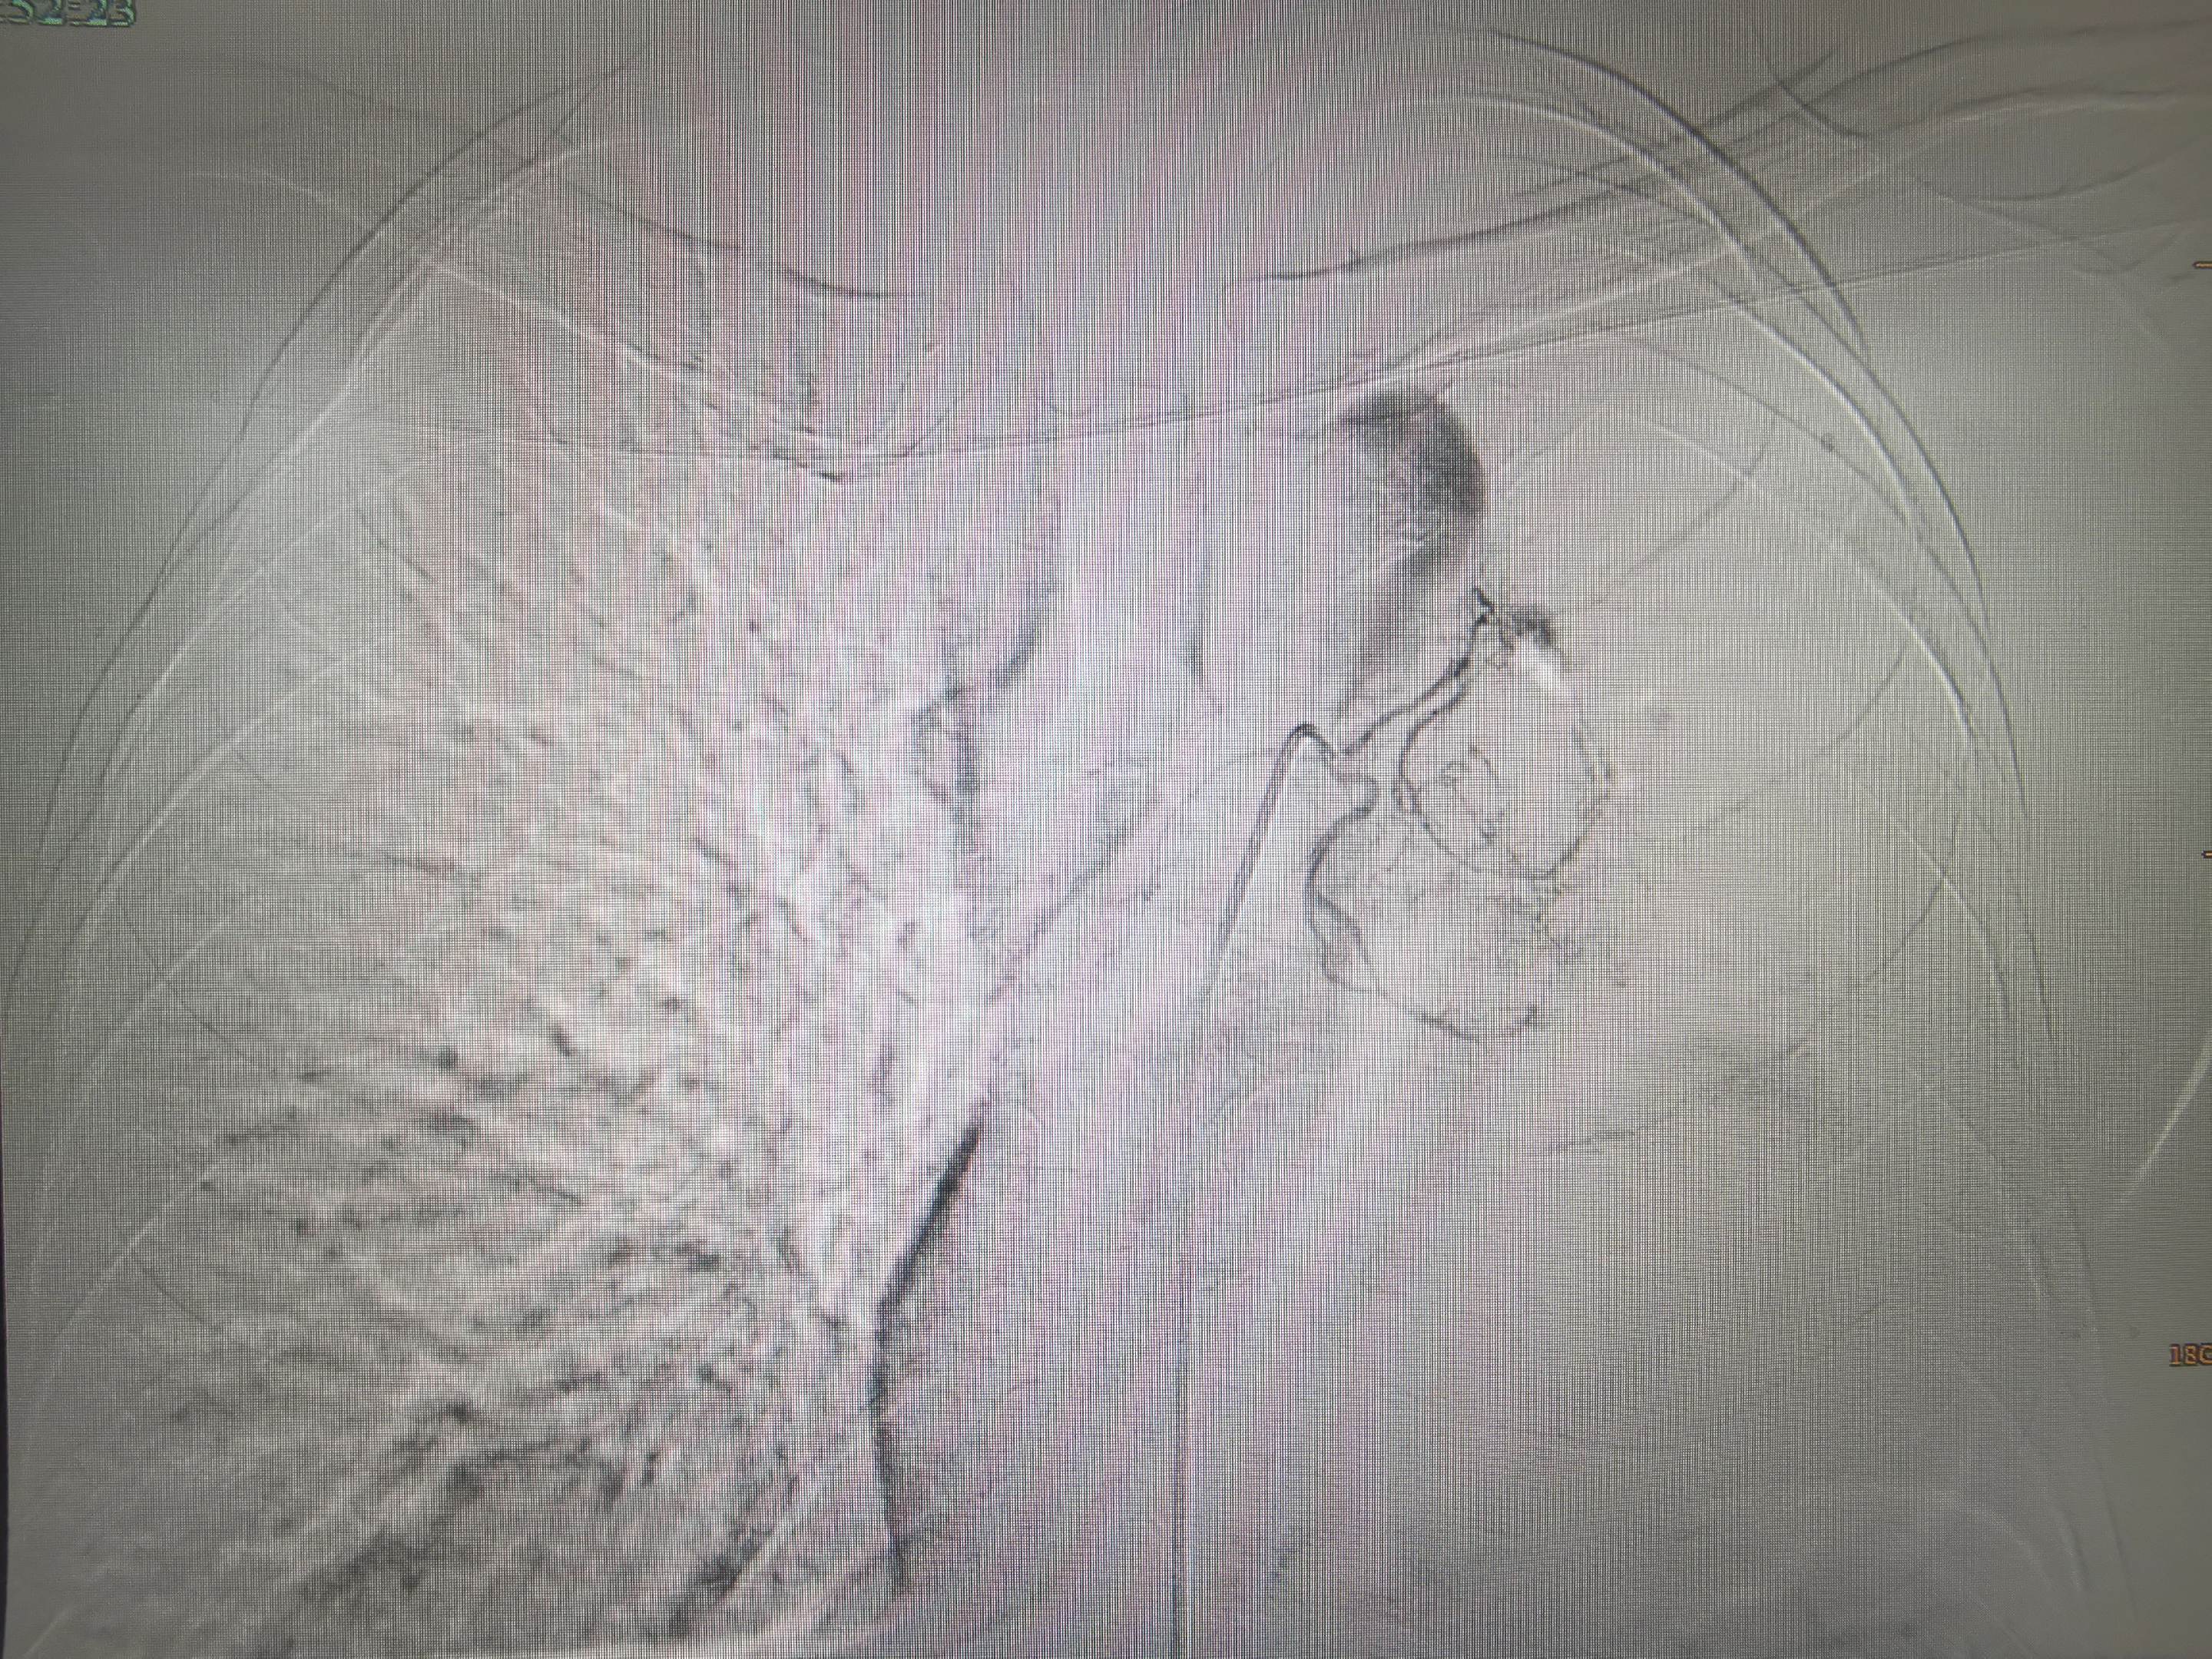

急诊咯血介入治疗,胸上动脉,锁骨下动脉分支,右侧支肋共干支气管动脉,右侧支气管动脉,食管固有动脉,左侧支气管动脉,右侧膈动脉,术前CTA以及选择合适的大导管和微导管真的重要,不仅能超选到位,又能快速完成超选。

左上肺癌,锁骨上动脉造影,甲状颈干分支供应左上肺癌,反复使用单弯导管无法勾到责任血管,单弯导管热蒸汽成形后成功找到责任血管,微导管超选后CBCT证实肿瘤染色丰富后进行微球栓塞。